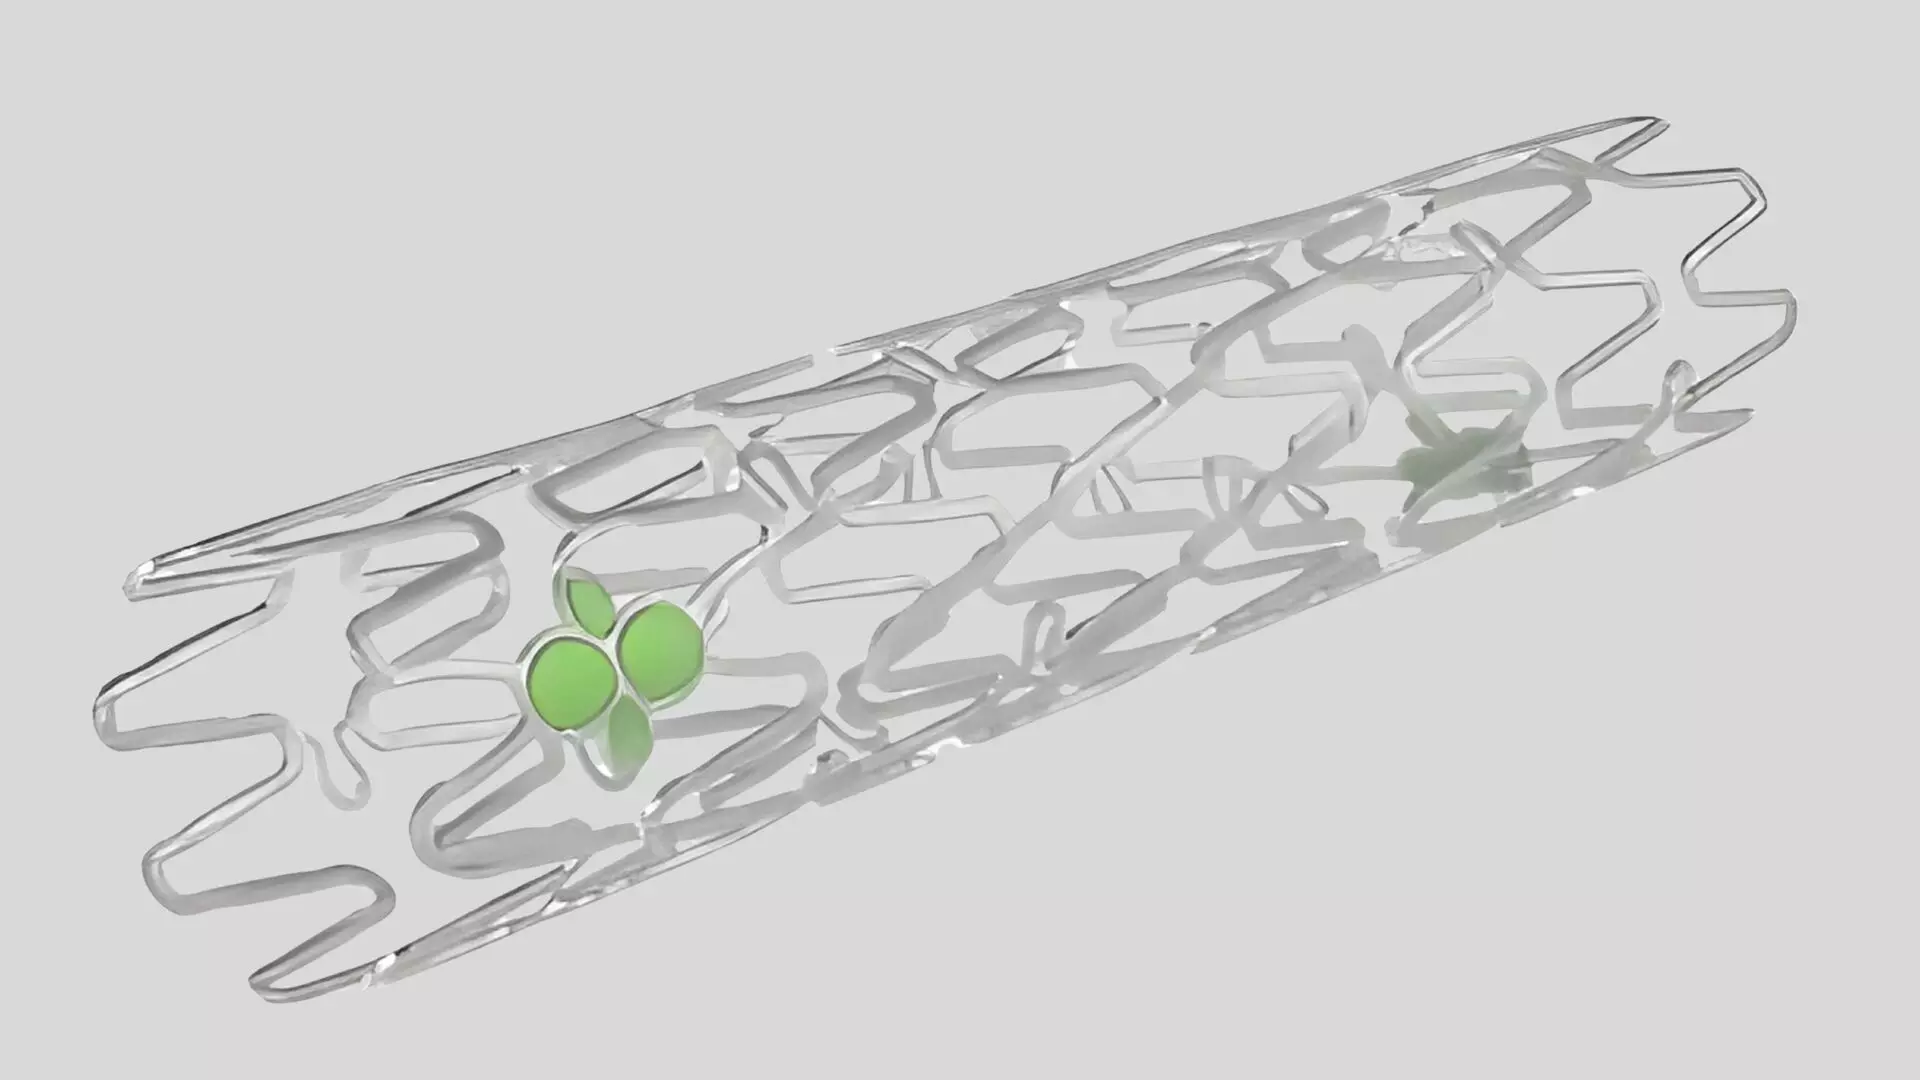

The IBS is a thin-strut (55–65 μm) bioresorbable scaffold made of Fe-0.05%N alloy as backbone material, coated abluminally with a PDLLA–sirolimus layer (8 μg/mm). It provides mechanical strength comparable to metallic stents and is designed to fully resorb over time, potentially reducing long-term risks such as late thrombosis or neoatherosclerosis.